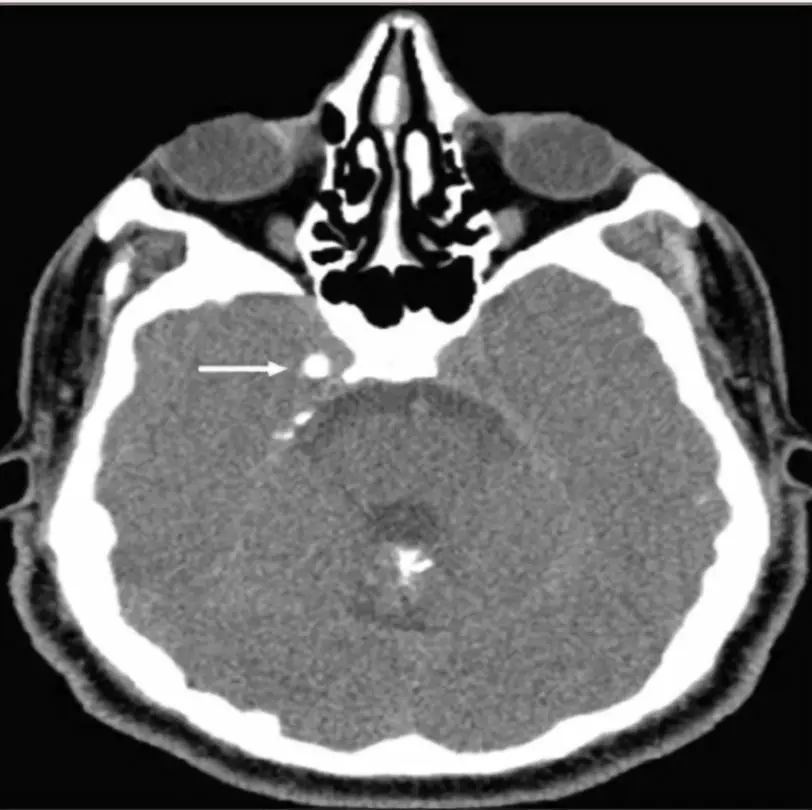

囊虫的钙化形态各异,取决于脑囊虫四个主要阶段(也称为Escobar的病理阶段):a囊泡期:活的寄生虫有完整的包囊膜,囊壁光滑,内可见头节,无强化。因此没有宿主反应。b胶状囊泡期:包囊破溃,包囊的液体渗入组织,周围有水肿。此期引发强烈的免疫反应,所以此期的临床反应最重。见下图。

c颗粒结节期:随着囊肿进一步变性缩小,水肿减轻;增强仍存在。d结节钙化期:终末期,静止的钙化囊残余;没有水肿。